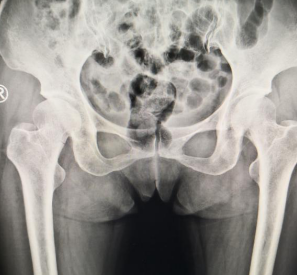

患者张先生,50岁,9月3日从自家车上下来时一脚落空,摔倒在地,右髋部着地,疼痛,无法站立行走,在当地医院摄片显示右股骨颈骨折,随后来到betway在线登陆关节科治疗。

蒋守海主任给患者做了仔细的体格检查,CT显示患者右股骨颈骨折,断端错位、成角,周围软组织肿胀。手术小组讨论后,决定采用骨科机器人辅助右股骨颈骨折复位内固定术,因传统的切开复位钢板内固定,患者创伤大,术后并发症多,手术费用高;采用骨科机器人辅助手术创伤小,术中出血少,更利于患者术后恢复。